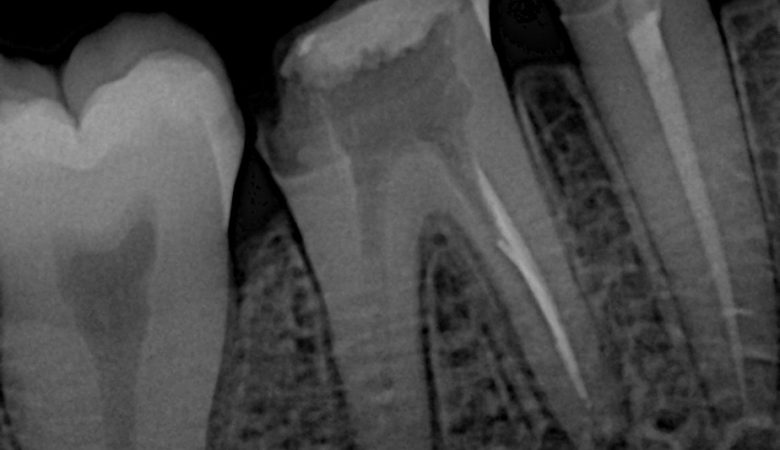

One-Year Follow-Up: Re-Endodontic Management with Deep Margin Elevation and Full Adhesive Rehabilitation of Mandibular First Molar Author: Dr. Hamza Zahid Clinic: Dr. Hamza Dental Center – Lahore, Pakistan Discipline: Endodontics | Restorative Dentistry | Adhesive Rehabilitation Tooth: #46 (Lower Right…